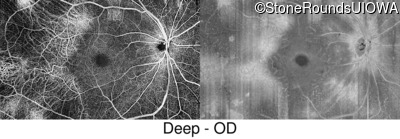

Swept-Source OCT - Right - 20/20 +1

Exemplar